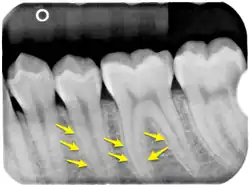

Die häufigste und seit vorgeschichtlicher Zeit nachweisbare[14] Krankheit der Zähne und des Menschen überhaupt ist die Zahnkaries (Zahnfäule). In Deutschland ist nur ca. ein Prozent der Erwachsenen kariesfrei, hat also naturgesunde Zähne.[15] Die Bemühungen mittels Gruppenprophylaxe und Individualprophylaxe führen zu immer besserer Zahngesundheit, insbesondere von Kindern und Jugendlichen, die mittels des DMFT-Index gemessen wird. Auch Erkrankungen des Zahnhalteapparats (siehe Zahnfleisch, Parodontitis) sind häufig. Ein seltenes Krankheitsbild ist die Tuberkulose der Zähne, bei der es durch zumeist bronchogene Streuung zu Entwicklung von tuberkulösen Zahngranulomen kommen kann. Orale, meist übersehene Befunde finden sich bei 1,4 % der an Tuberkulose Erkrankten.[16]